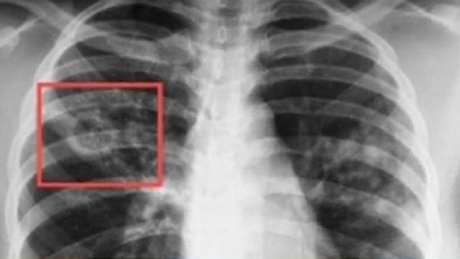

В поддержку инициативы Всемирной организации здравоохранения в России ежегодно 24 марта проводится Всемирный день борьбы с туберкулезом. Лозунг этого дня в 2016 году – «Вместе ликвидируем туберкулез!».

По данным ВОЗ, туберкулез входит в число трех основных причин смерти лиц в возрасте 15–44 лет. Учитывая распространенность туберкулеза, угроза заразиться и заболеть сегодня существует для каждого. Заболевший человек является источником инфекции для окружающих, и прежде всего для детей, беременных и лиц со сниженным иммунитетом. В то же время при проведении профилактических мероприятий это заболевание можно предотвратить, а при раннем выявлении и правильном лечении полностью излечить.

Борьба с туберкулезом сегодня – важнейшая задача государства и всего общества. В результате принимаемых мер показатели заболеваемости и смертности от туберкулеза за последние годы постепенно снижаются. Заразиться им может каждый, но наиболее высокий риск имеют люди, находящиеся в тесном контакте с больным активной формой туберкулеза. Источниками туберкулезной инфекции являются больные люди или животные, выделяющие во внешнюю среду микобактерии туберкулеза.